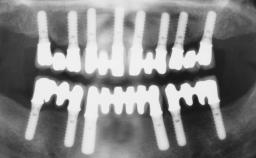

Immediate Loading of Six Implants in the Maxilla and Final Restoration with a Full-Arch Gold/Ceramic FDP Involving the Concept of Tilted Implants

# of Implants 6

Bone Augmentation Horizontal|Simultaneous

Bone Volume Deficient horizontally, allowing simultaneous augumentation